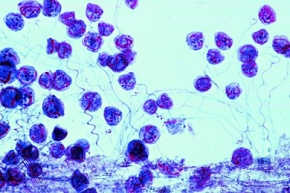

Mikropräparat - Trypanosoma cruzi, Leishmania-Formen, Gehirn der Maus quer

Mikropräparat - Trypanosoma cruzi, Leishmania-Formen, Gehirn der Maus quer